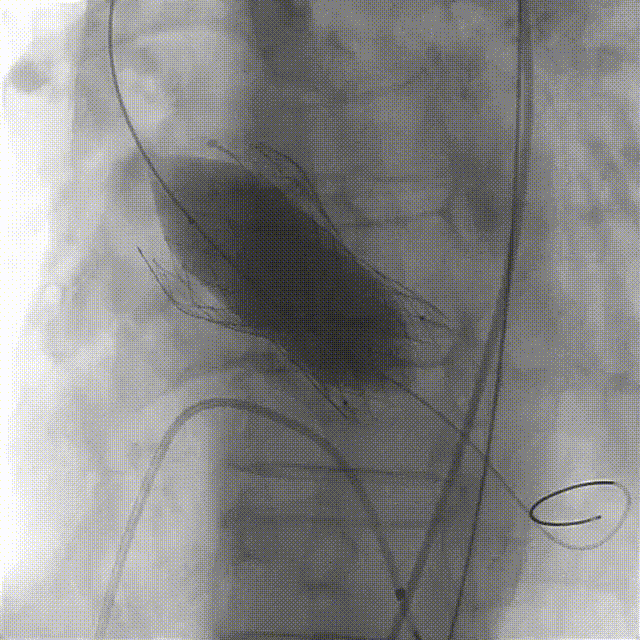

主动脉根部造影,左右冠脉显影明显,有少中量反流。

主动脉根部造影

导丝跨瓣极其困难,因其Type0型二叶瓣的独特结构,加之不均匀的钙化分布,引起瓣膜的贴合不良,难以找到准确的瓣口,多次弹出,最后成功过瓣后显示路径有明显弯度。

导丝跨瓣